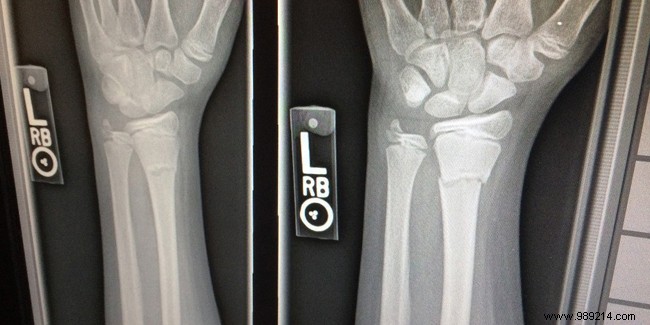

It commonly affects the spine, wrists, hips, pelvis, and shoulders, increasing the risk of fractures.

Known as the 'silent disease,' osteoporosis often progresses without pain or obvious signs until a fracture occurs, typically from a minor fall. Warning signs include vertebral compression fractures, leading to stooped posture (kyphosis) and noticeable height loss.

Diagnosis involves bone densitometry, a reliable scan measuring bone density.